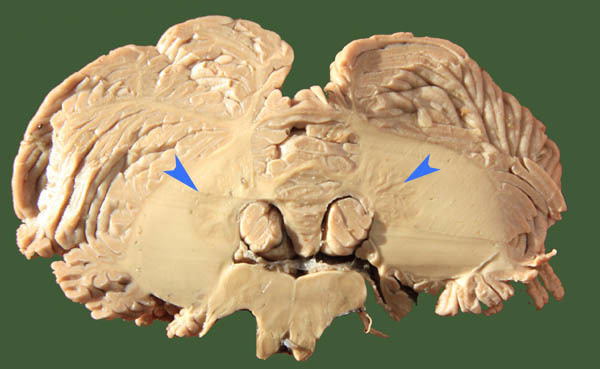

What is this nucleus and what does it do?

This is the dentate nucleus - largest and only visbile nucleus in a living specimen

-planning, intiation and control of movement

What is the fissure called that separtes the anterior and posterior lobes?

Primary fissure

what are the cerebellar deep nuclie in order from medial to lateral?

fastigule, interpose and denate